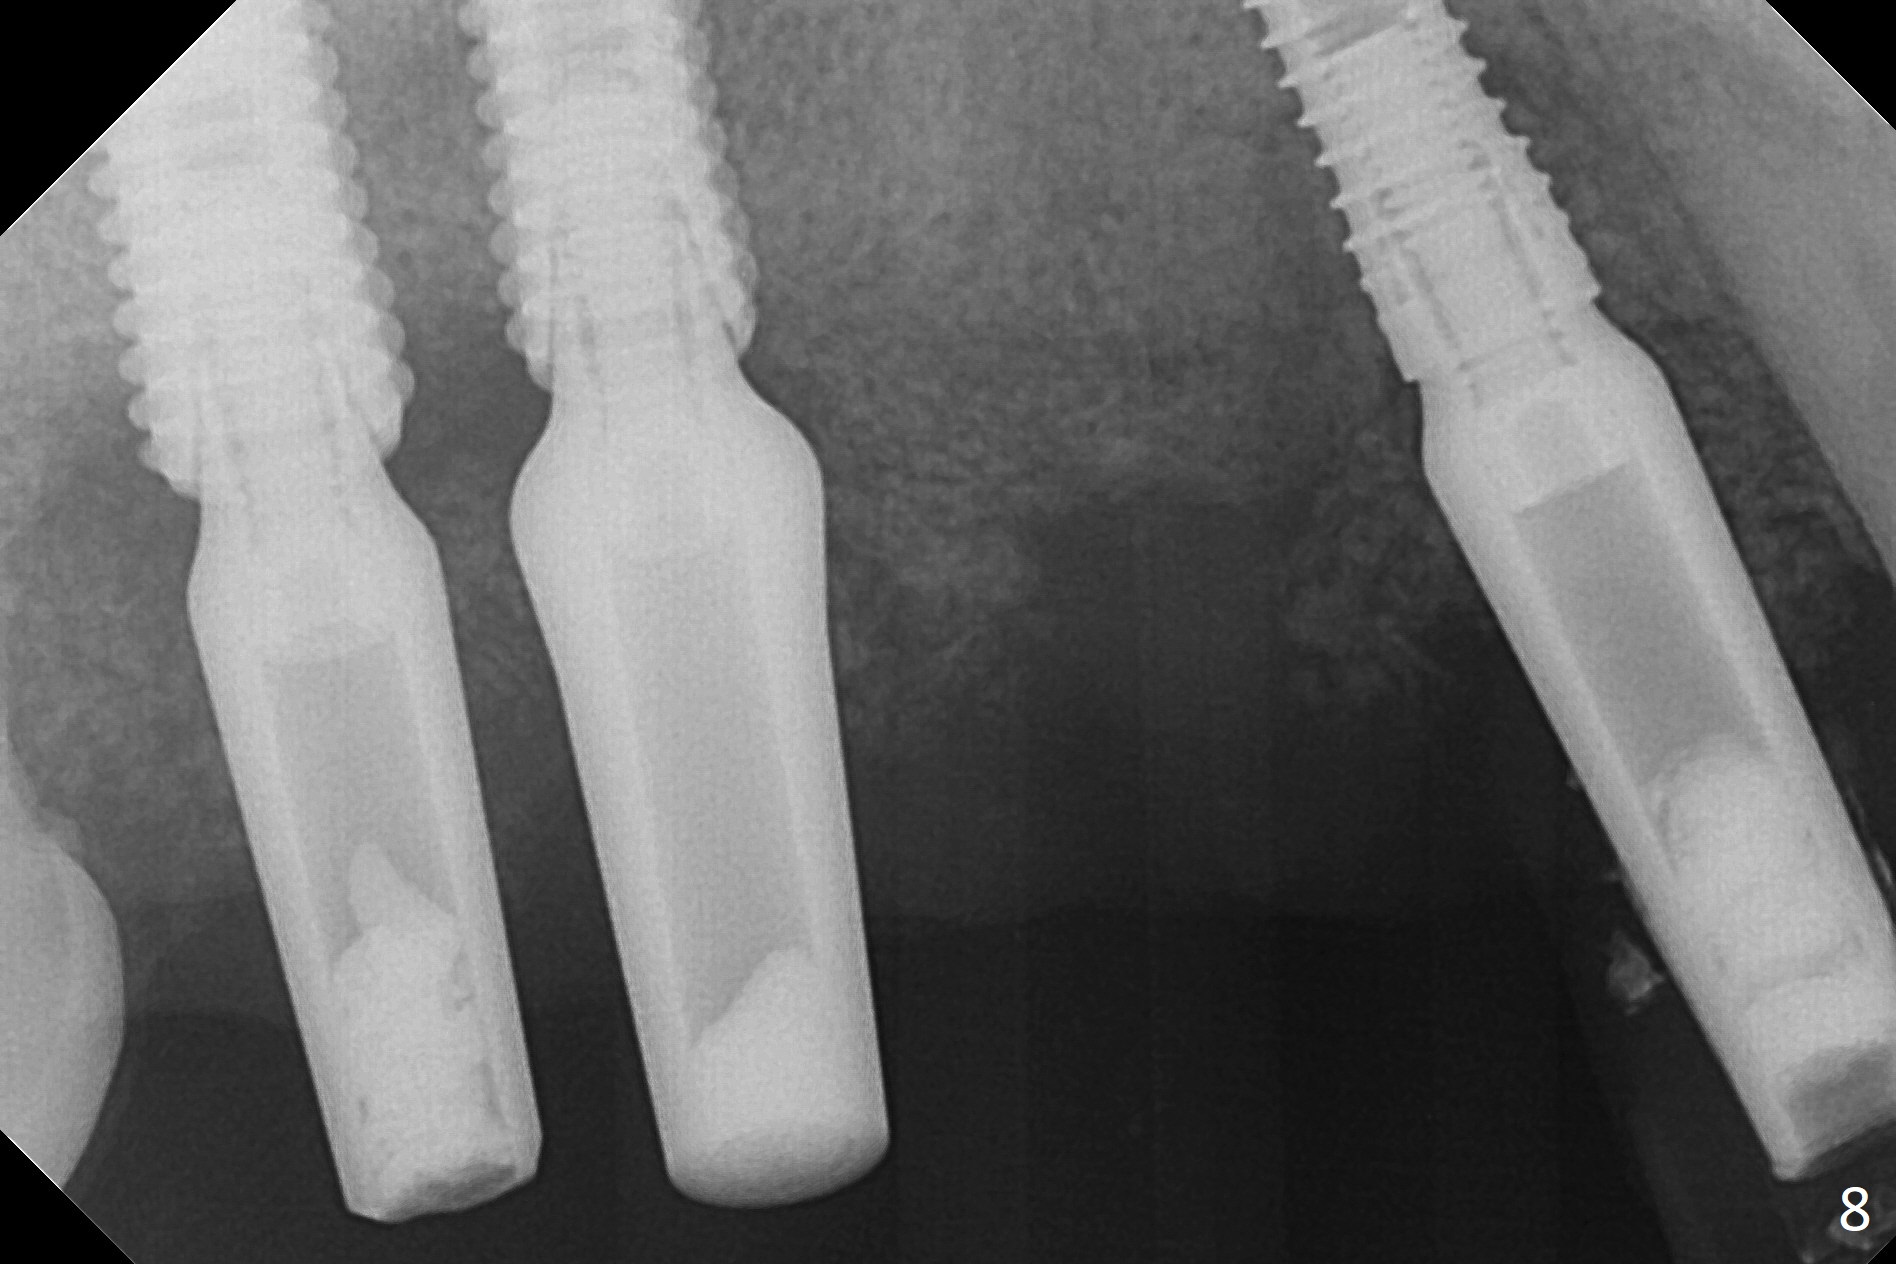

After extraction, the depths of initial osteotomy at #2, 3 and 5 are 13, 11.5 and 10 mm, respectively (Fig.1). Following adjustment of trajectory, a 3.8x13 mm UF implant is placed at #5 (Fig.2) with insertion of a 4.5x2 mm mill abutment as well as mineralized cortical/cancellous allograft (Vanilla, *). The mill abutment is chosen because the margin of a 5.5x7(5) mm cemented abutment is severely subgingival (Fig.4 at #3; ^ gingival margin). By the same token, a 4.5x3 mm mill abutment is placed at #2. In fact all of the 3 implants are placed 2-3 mm out of the bone (Fig.5). To prevent periimplantitis, abundant allograft is placed around the implants/abutments (Fig.2,4 *). Nearly 2 months postop, the mill abutment at #2 is adjusted for its height, while a 5.5x2.5 mm mill abutment is placed at #3 (Fig.6). To regain the buccal gingiva, the buccal margin of the provisional is shortened (Fig.6,7). Two weeks later, the gingival regrowth is not obvious (Fig.8 (nearly 3 months postop)). Local poor oral hygiene remains. A provisional FPD is fabricated. If his occlusion is normal for another 2 weeks, impression will be taken for upper (or UL) permanent restoration.